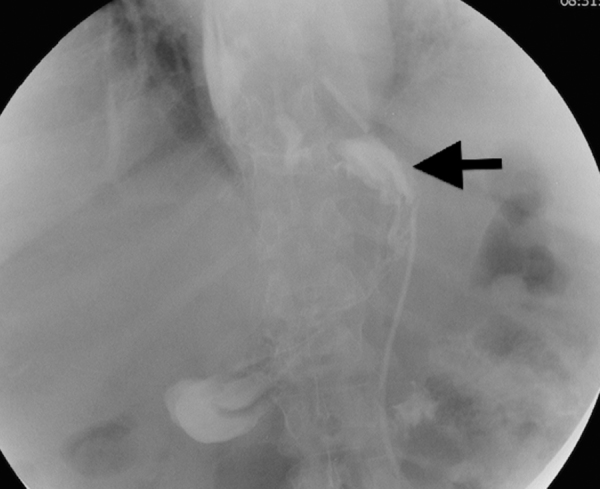

A 57-year-old female patient presented to the department of surgery with mild intermittent gastric pain and reflux. Two years previously, she had undergone a SG for morbid obesity (BMI 50). Preoperative studies of upper gastro intestinal (UGI) >series and gastroscopy were normal. Peroperatively, the left diaphragmatic crus was seen, the greater curvature of the stomach was released and the whole fundus was excised, no hiatal hernia was identified. A postoperative UGI showed a narrow gastric tube with no other abnormalities (Fig. 1). The patient lost around 45 kg 1 year postoperatively. Two years later, the patient was complaining of mild epigastric pain. An enhanced CT scan showed a trans-hiatal hernia of the gastric tube (Fig. 2). Taking into consideration her symptoms and a moderate weight regain, a decision to convert the SG to a gastric bypass was validated in a multidisciplinary team meeting [2]. This conversion to a gastric bypass was performed with reduction of the gastric pouch, closure of the posterior crural orifice with interrupted non absorbable sutures, fashioning of a 30 ml gastric pouch, and a manual gastrojejunal anastomosis. Her postoperative course was uncomplicated. The patient had lost 28 kg at 6 months postoperatively.

Fig. 2.

Gastric volumetry by gastric tomography. Arrow: pouch hiatal hernia.